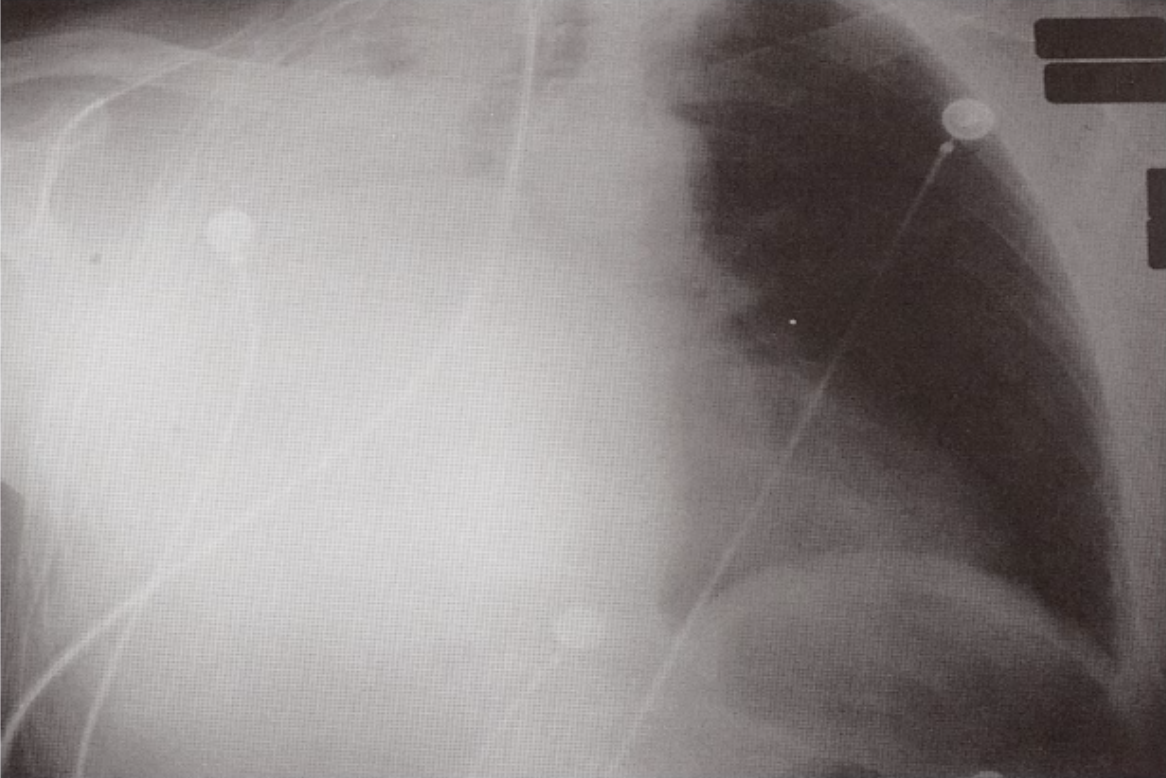

What does this CXR show?

Cardiomegaly/Pericardial Effusion

Heart size > 50% of the lung fields.